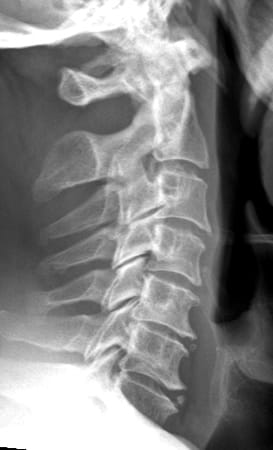

Auf diese Weise wird die Belastung der Wirbelsäule wie bei einer natürlichen Bandscheibe aufgenommen. Bei chronischen Bandscheibenerkrankungen sollte zuvor eine mindestens 3-monatige konservative Therapie versucht werden. Ist diese erfolglos oder treten nicht beherrschbare Schmerzen oder Nervenstörungen auf, so übernehmen die Krankenkassen in der Schweiz die Operation, sofern nicht mehr als zwei Bandscheiben betroffen sind und keine primäre Arthrose der Facettengelenke vorliegen. Bei akuten Bandscheibenvorfällen mit schweren Nervenstörungen oder Lähmungen besteht ebenfalls die Indikation zur Operation. Diese wird von vorne durch einen kleinen, etwa 2-3 cm langen, queren Hautschnitt in einer Hautfalte am Hals vorgenommen. Rechts oder links seitlich der Luft- und Speiseröhre gelangt man sehr schonend auf die Halswirbelsäule. Auf diese Weise kann die betroffene Bandscheibe vollständig entfernt werden und der Rückenmarkskanal sowie die entsprechenden Nervenwurzeln entlastet werden. Anschließend wird der Bandscheibenraum mit speziellen Instrumenten auf seine normale Höhe aufgedehnt, um die Nervenwurzeln zu dekomprimieren und Platz für die Prothese zu schaffen. Nach Ausmessen der passenden Größe und präziser Vorbereitung des Implantatbettes wird das Implantat unter Röntgenkontrolle eingesetzt. Beispiel einer degenerativen Bandscheibenerkrankung an der HWS und Versorgung mit drei visko-elastischen Bandscheibenprothesen

vor OP seitlich